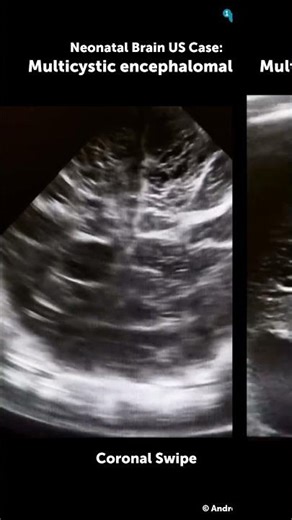

Neonatal Brain Ultrasound Case: Multicystic encephalomalacia

YouTube

123sonography

已浏览 3456 次

2 周前

123sonography on Instagram: "Here's a new neonatal/pediatric brain ultrasound case presented by our Ambassador Andrei Satsuk 🩺 A 1-month-old, born full-term, now admitted for poor feeding, seizures, and profound developmental delay. At birth, the infant suffered severe hypoxic-ischemic encephalopathy following placental abruption and was treated with therapeutic hypothermia. The brain US study reveals severe, bilateral multicystic encephalomalacia. What are the sonographic features of this dise